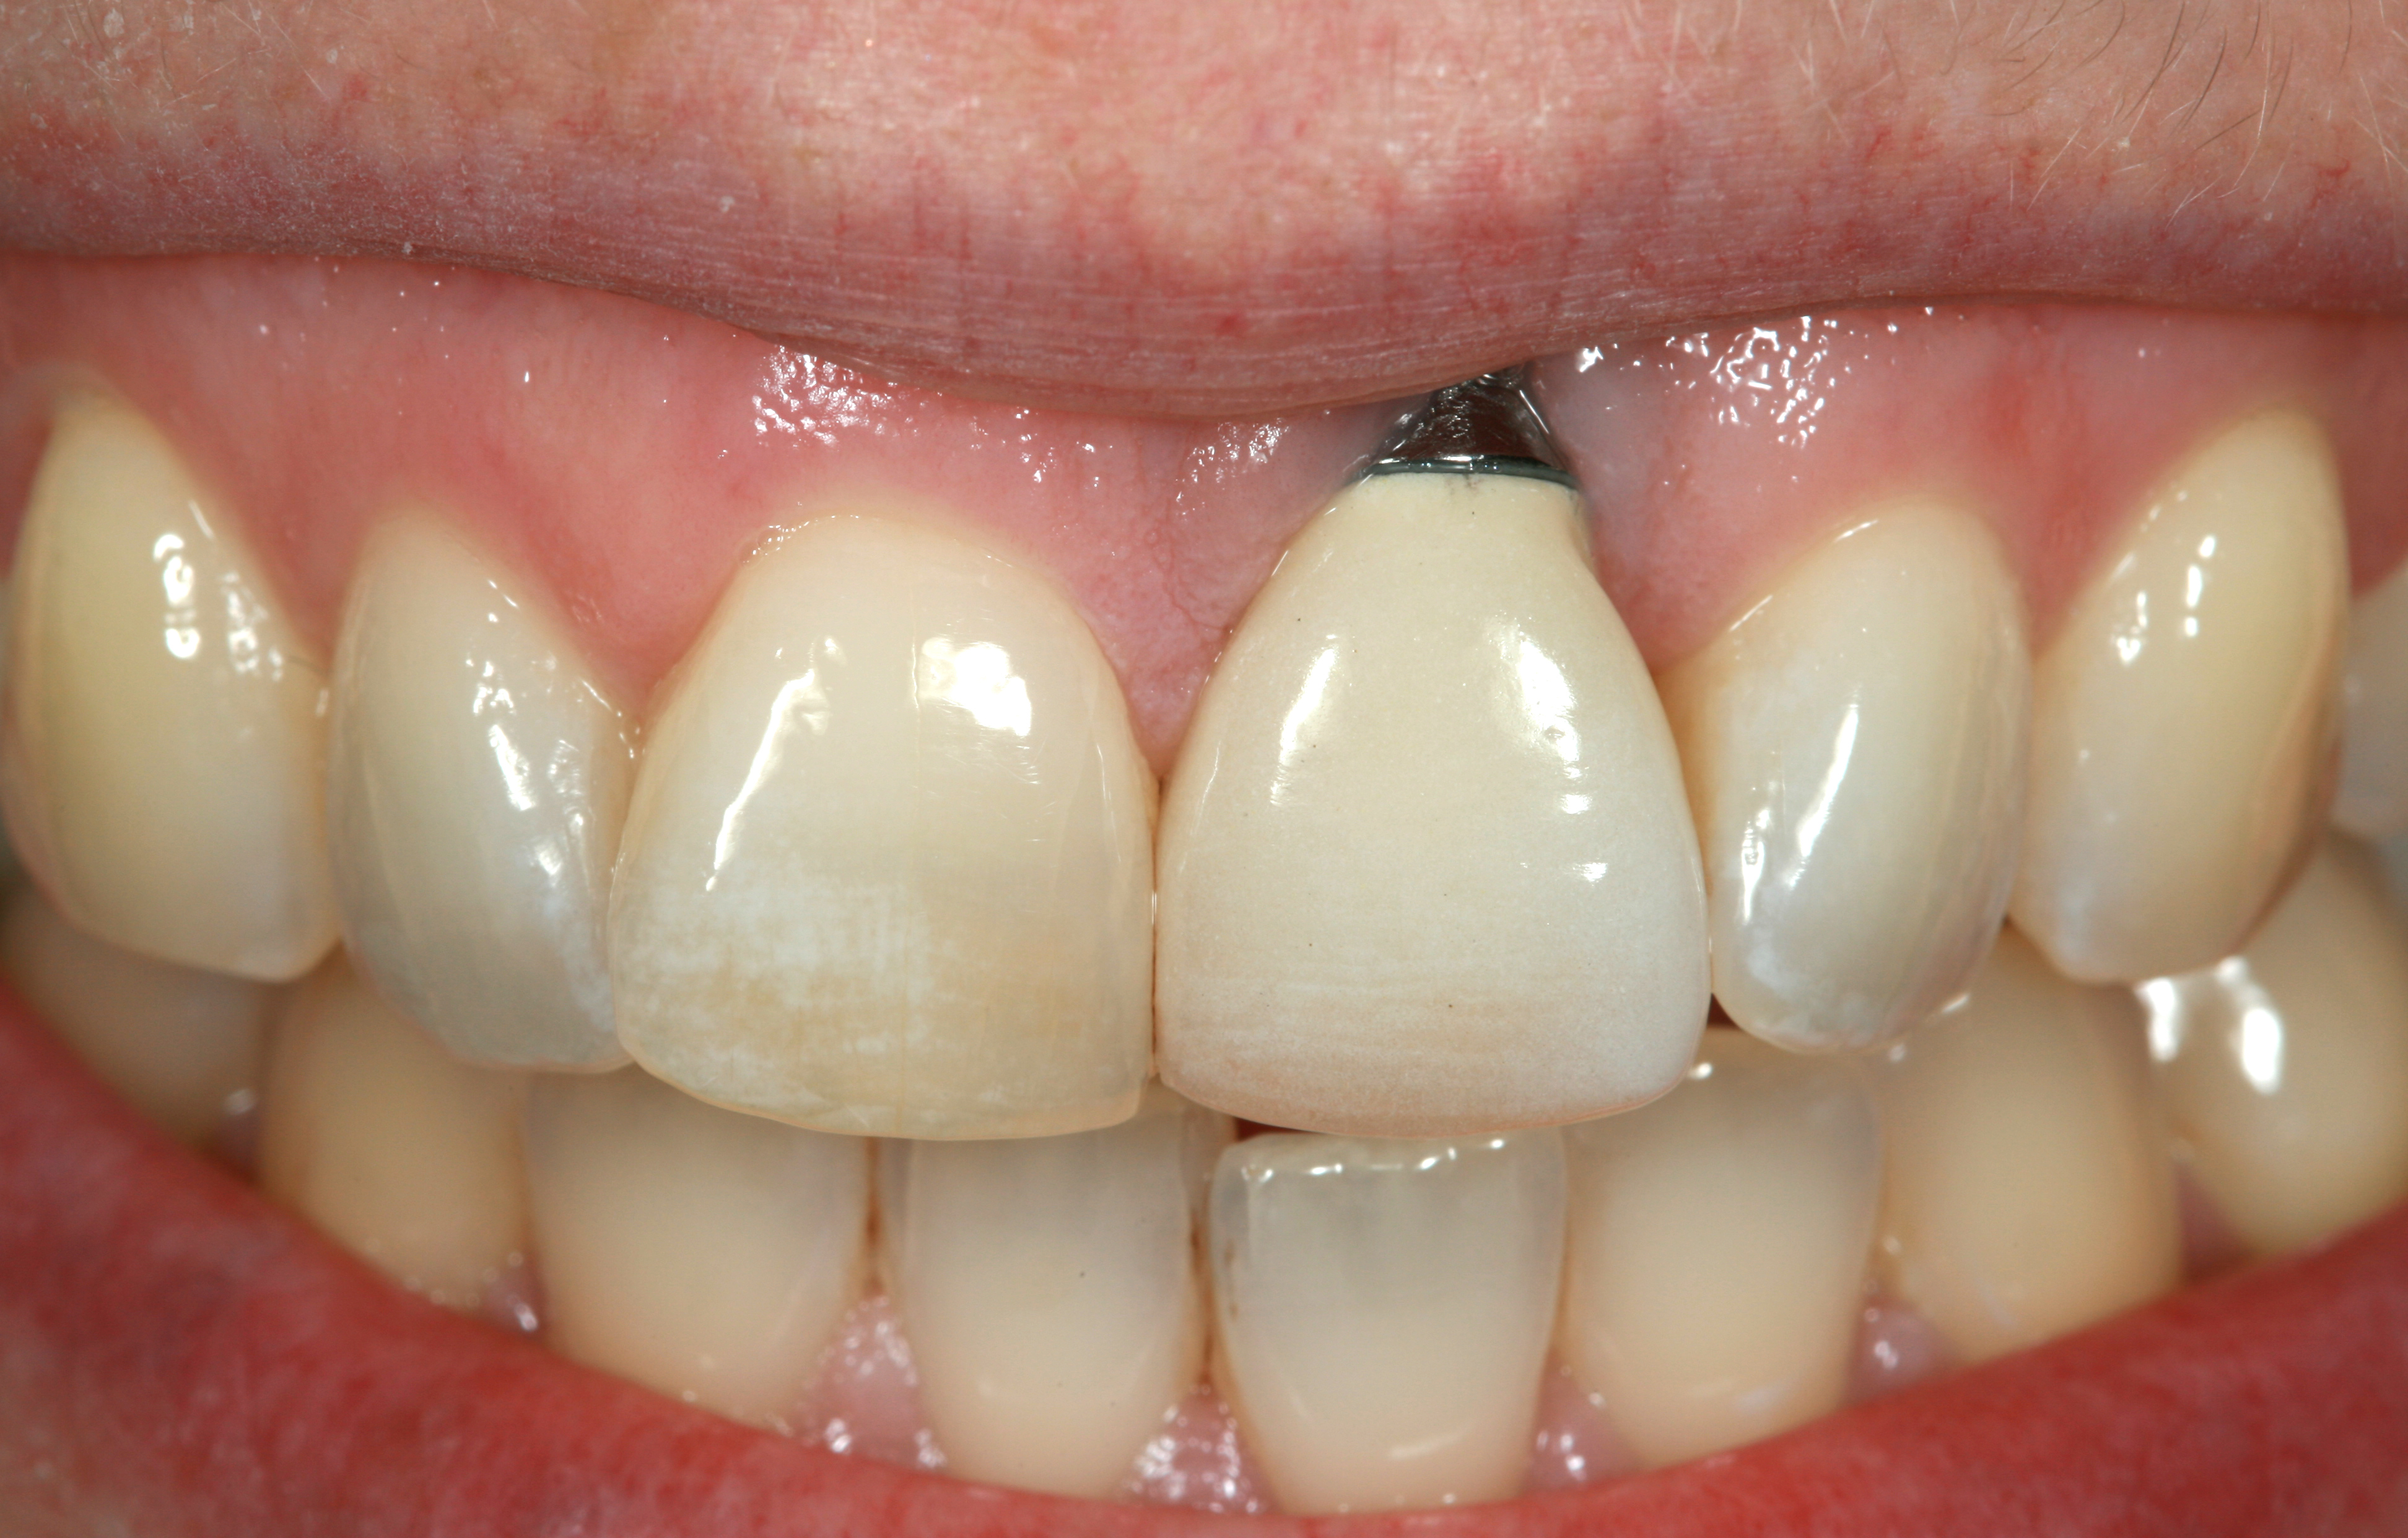

Fig 47. Implant tooth No. 9 was placed too close proximally to tooth No. 10. The result was violation of interproximal biologic width and loss of interproximal attachment that clinically translated into loss of the interdental papillae.

Figure 47

Fig 48. Radiograph of implant in the area of tooth No. 9 in Figure 47. Note the close proximity of the implant No. 9 to tooth No. 10.

Figure 48